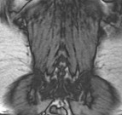

MRT – auch Kernspintomografie, oder Magnetresonanztomografie genannt – ist eine diagnostische Technik zur Darstellung der inneren Organe des menschlichen Körpers. Hier haben wir ein paar Bilder, um zu zeigen wie solche Aufnahmen mit dieser Technik aussehen.

Die Bilder sind nicht für diagnostische Zwecke geeignet!